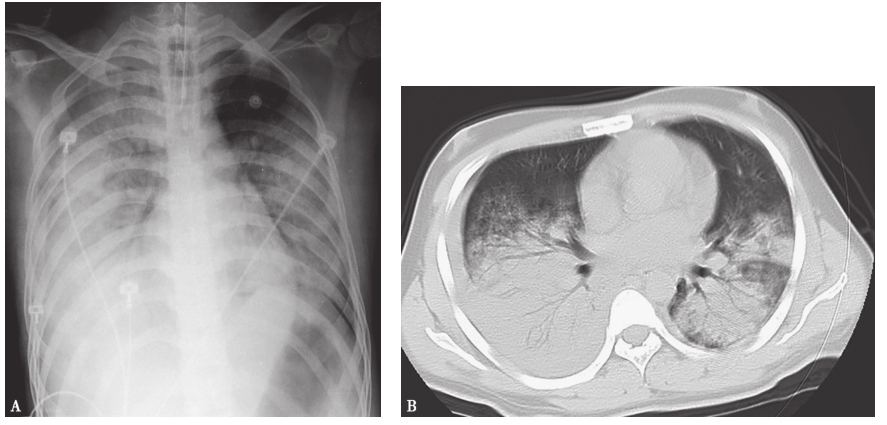

胸部CT:左肺下叶病灶边界较为清楚,表现为实变、空洞,空腔病灶内有液平(图13),其脓液界面呈类蜂窝状气囊影改变。

图13 入院后胸部CT表现(发病后37天)